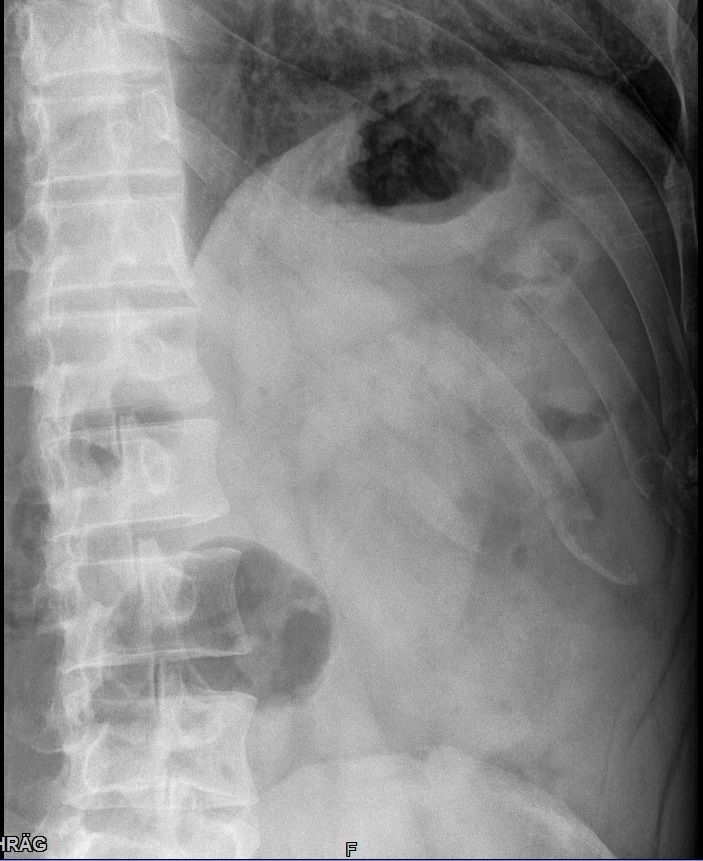

Fehler

Schneidet der seitliche Filmrand die laterale Thoraxwand ab, evtl. durch zu schmales Filmformat oder unzureichend gute Positionierung, so wird der so wichtige Thorax-Zwerchfell-Winkel (Sinus phrenico-costalis) nicht abgebildet. Eine alte oder eine kleine frische Brustfellentzündung wird auf einer solchen Aufnahme übersehen.

Abhilfe

Man muss den Patienten so stellen, dass der rechte und linke Kassettenrand noch seitlich vorstehen und die Blende nicht abschneidet.